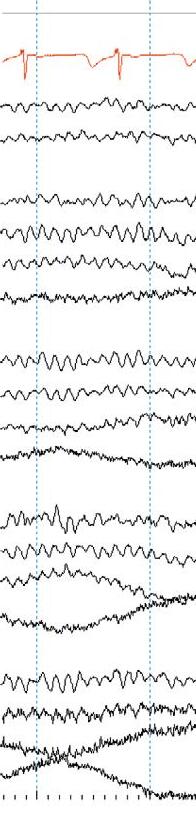

Thekeytolocalizationisanelectrographicprinciplecalleda phasereversal. ThisisasimultaneousbutoppositedeflectionintwoadjacentEEGchannels containingacommonelectrode.Aphasereversalimpliesthatthecortical potentialismaximalatthelocationofthecommonelectrode.

Mostphasereversalsarenegative(><),thoughrarelypositivephase reversals(<>)mayoccur. Figure1.4 showsanexampleoflocalizingafocal sharpwave.

Figure1.4 Localizingasharpwave(blackarrow)throughphasereversaltoelectrodeP8(blackcircle).